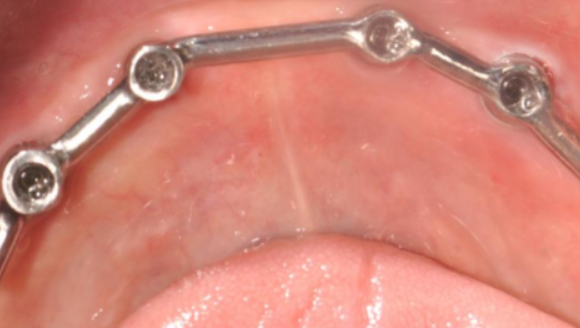

1. 固定原理差异:Locator是在单颗种植体上安装“按扣”装置,患者能像安装手机壳一样自行摘戴;而杆卡需要2颗以上种植体用金属杆连接成轨道,义齿沿轨道滑动,取戴时需要医生协助。

2. 杆卡操作特点:手术时间比Locator多10分钟,因为需要连接金属杆。金属杆需要进行年度检查,这是免费的,而且10年左右可能需要更换金属杆。